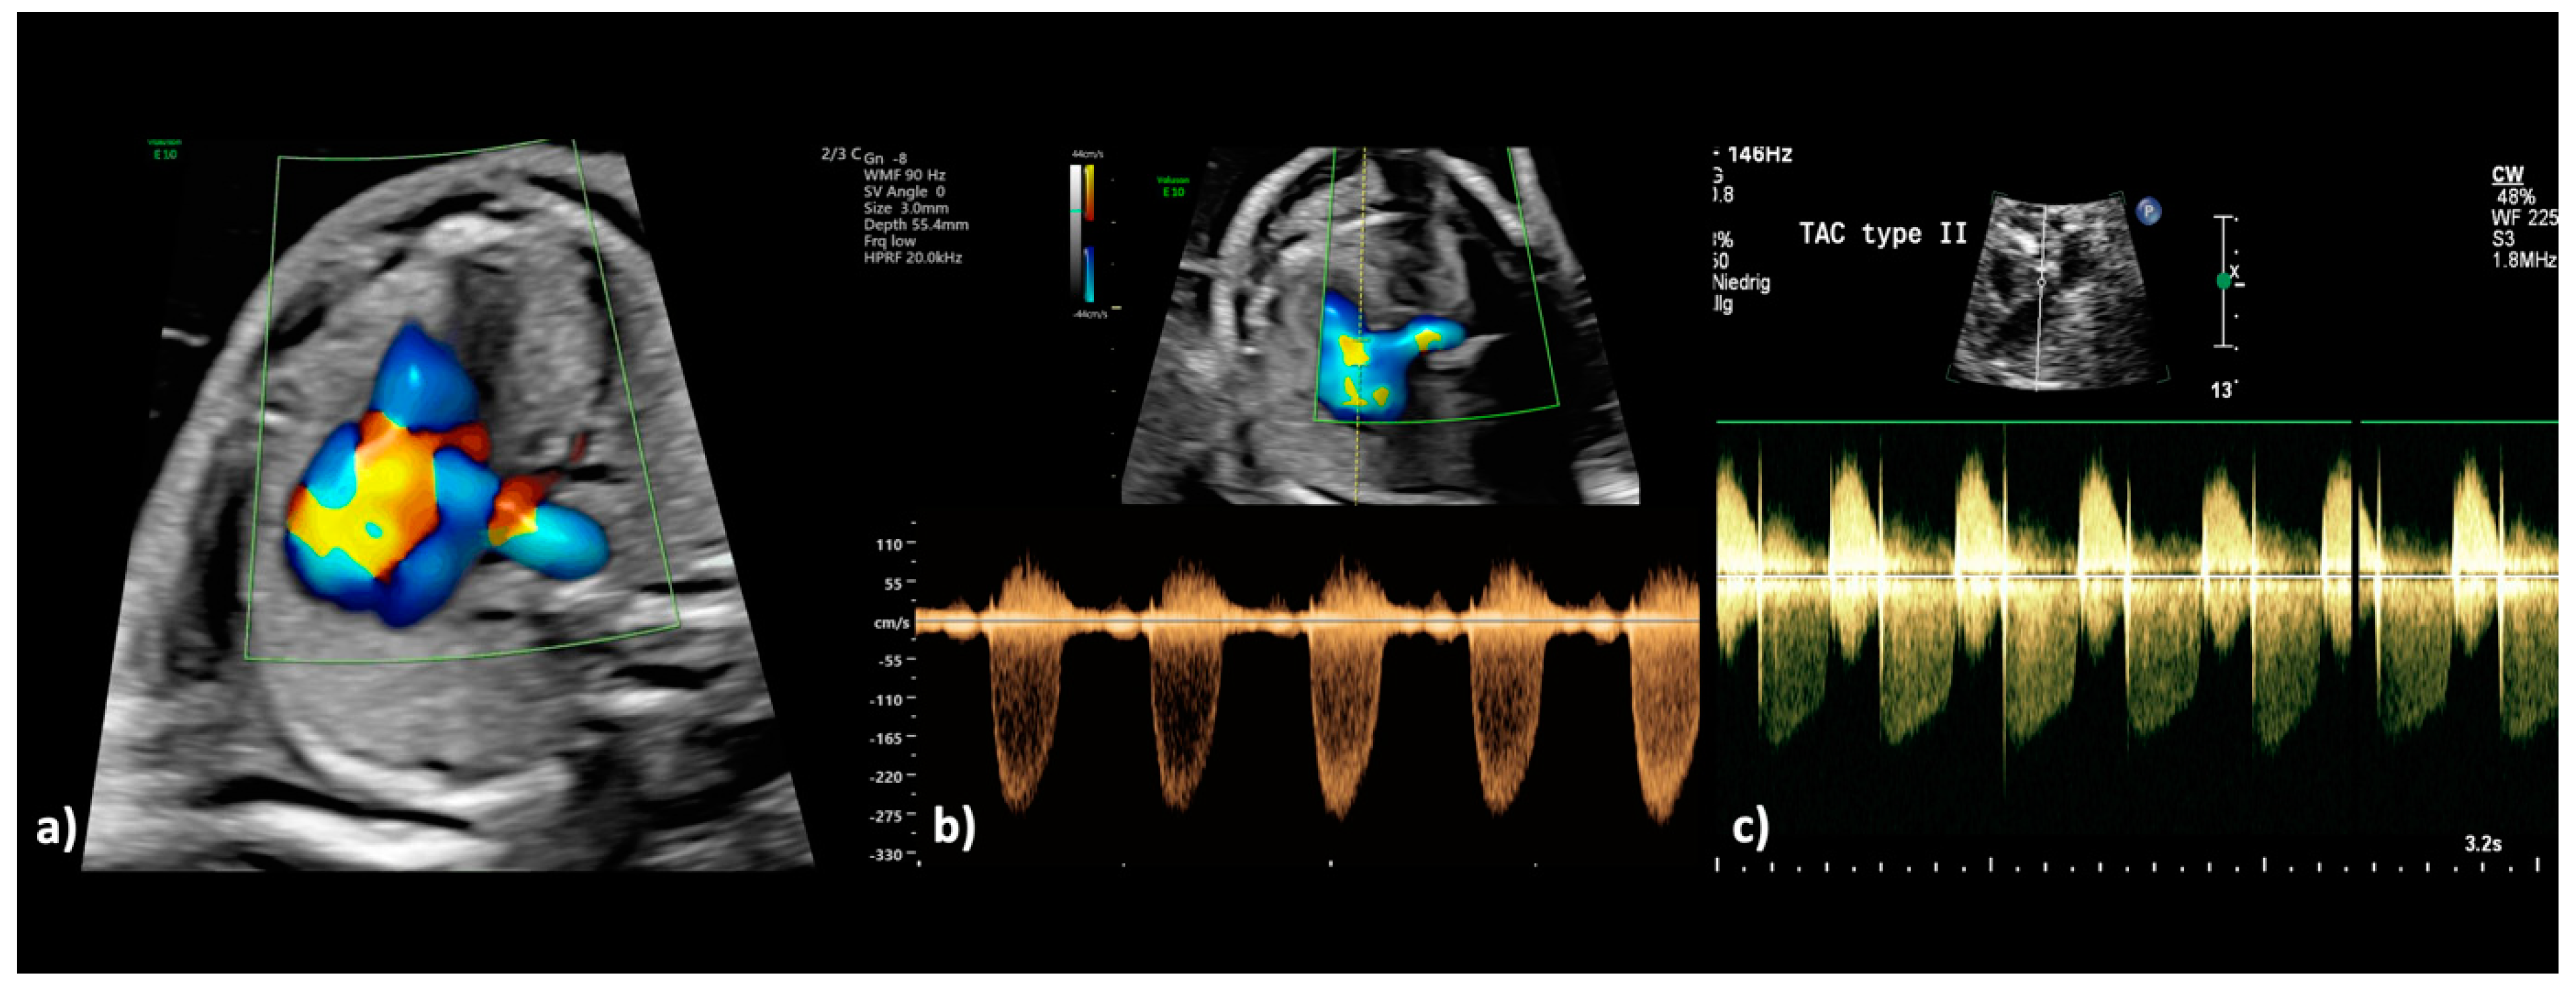

Figure 4.

(a–c): Truncus arteriosus type 1 at 22 + 0 weeks. (a) In the color Doppler mode, the filling of the common arterial trunk from both ventricles and the confluent origin of both pulmonary arteries from the posterior side of the aorta is visualized (aortic dominance), as well as aliasing and high variance as indications of disturbed blood flow due to stenosis of the truncal valve. (b) The spectral Doppler examination confirms the presence of a stenotic truncal valve by a high maximum velocity (peak systolic velocity: 3.0 m/s; maximum pressure gradient (ΔPmax: 36 mm Hg) and wide variation of the blood flow. (c) In another fetus with truncus arteriosus type A2 at 34 + 1 weeks, there is both a relevant stenosis and a severe regurgitation of the truncal valve; during systole, the tubular antegrade flow with a peak velocity of 2.40 m/s can be recognized; during diastole, the insufficiency of the truncal valve with a peak velocity of 3.30 m/s can be recognized.